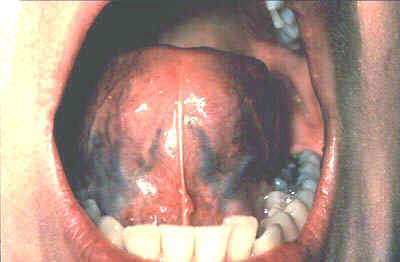

Con la lengua del

| También tenga en cuenta cualquier cambio en el patrón de las papilas que cubre la superficie de la lengua y también examine la punta de la lengua. El paciente deberá protruir la lengua, y el examinador deberá tener en cuenta cualquier anormalidad en la movilidad o posicionamiento. |

| Con la ayuda del espejo bucal, inspeccione los márgenes laterales derecho e izquierdo de la lengua. |

| Tomando la punta de la lengua con un pedazo de gasa ayudará a la protrusión completa y permitirá el examen de la región posterior de los bordes laterales de la lengua. |

| Examine la superficie ventral. Palpe la lengua para detectar su consistencia. |